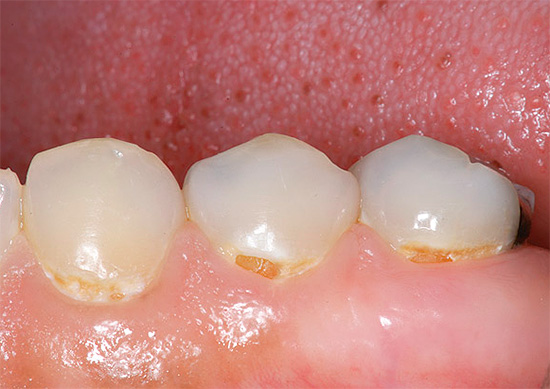

- Una diminuzione della concentrazione di calcio e composti del fluoro sia nella saliva che nel sangue a causa di un certo consumo per le esigenze di un embrione in via di sviluppo. Allo stesso tempo, il calcio non viene consumato dai denti stessi, come molti credono in modo errato. Ma la rimineralizzazione dello smalto e il suo rafforzamento, che si verificano sempre in altri periodi a causa dell'azione della saliva, durante la gravidanza possono rallentare o addirittura arrestarsi. Di conseguenza, lo smalto diventa debolmente mineralizzato e viene più facilmente danneggiato dai rifiuti acidi prodotti dai batteri.

Pertanto, a proposito, è così importante vedere un dentista durante la gravidanza - se la carie viene rilevata nelle primissime fasi del suo sviluppo, il trattamento può essere effettuato utilizzando metodi di remineralizzazione senza anestesia, senza trapano e sensazioni spiacevoli. Ma la carie già lanciata senza anestesia guarirà davvero.

La carie durante la gravidanza non può solo essere curata, ma è anche necessaria. A volte, a causa del rischio di sviluppo acuto della malattia, il trattamento tempestivo per alcune donne in gravidanza è l'unico modo per prevenire carie generalizzata. Naturalmente, la gestione stessa della malattia dovrebbe tenere conto della posizione del paziente.